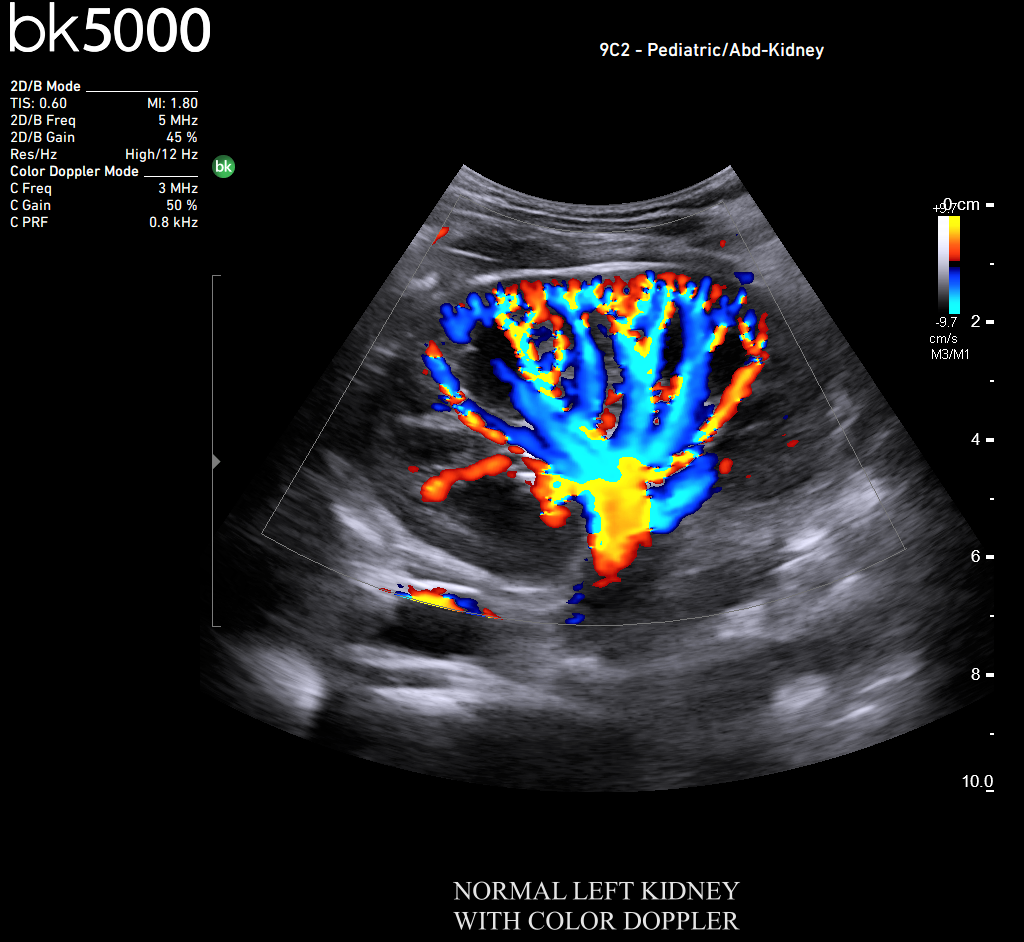

High Resolution Imaging

You know what you need, and you need it fast. That’s why the bk5000 is designed to deliver the high resolution images you count on quickly and efficiently. Whether you’re identifying margins of a lesion or making a general assessment of an area of interest, the bk5000 has the power and performance to meet your needs on your terms.